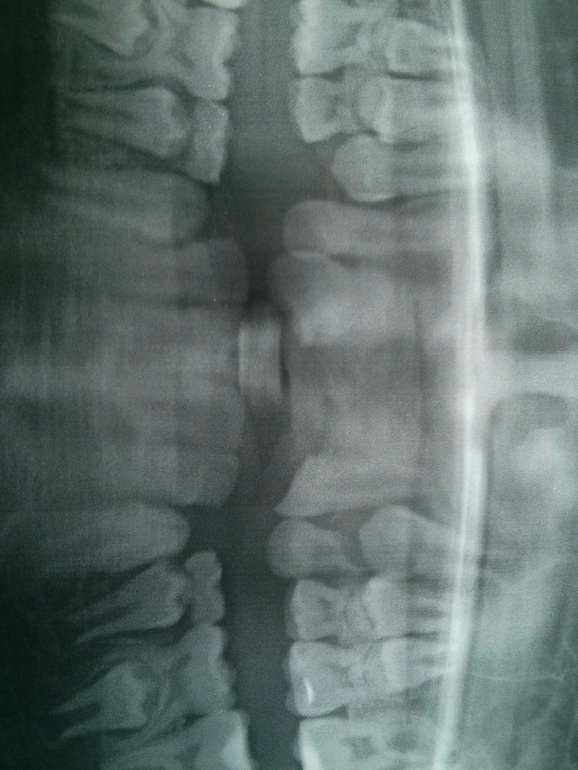

Добрый вечер. 3 недели спустя после аварии пошли сегодня к врачу. И оставшийся передний зуб из пары остался подвижным Сделали повторно снимок, а там вот это(

07.10.2019

Добрый вечер! Перелом корня. Увы, его тоже, наверное, на выход.

Вот и нам так сказали😖 Из вариантов замещения только пластина, были 2х врачей, говорят больше вариантов нет(( Сходим ещё к одному, конечно